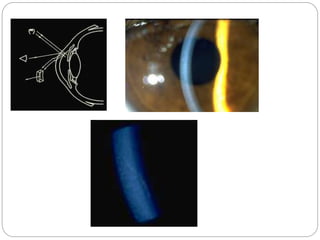

Optic section

 Optic section is a very thin parallelepiped and

optically cuts a very thin slice of the cornea.

 Axes of illuminating and viewing path intersect

in the area of anterior eye media to be

examined e.g. the individual corneal layers.

 Angle between illuminating and viewing path

is 45 degree.

 Slit length should be kept small to minimize

dazzling the patient.

 With narrow slit the depth and portion of

different objects(penetration depth of

foreign bodies, shape of lens etc) can be

resolved more easily.

 With wider slit their extension and shape

are visible more clearly.

 Magnification: maximum.

 Examination of AC depth is performed by

wider slit width .1-.3mm .

 Used to localize:

Nerve fibers

Blood vessels

Infiltrates

Cataracts

AC depth.

Optical section of lens

1.Corneal scar with wide beam illumination 2.optical section through scar

indicating scar is with in superficial layer of cornea.